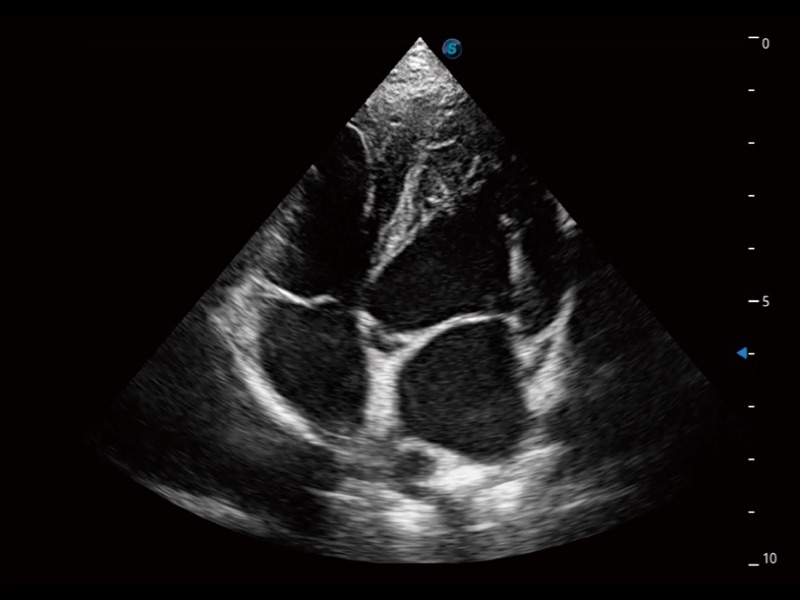

猫、中小型犬及小型异宠动物

ProPet 70专为动物医生设计,对不同的动物体型和生理结构作出了针对性的优化。通过动物影像专用软件,可满足个性化的应用需求,帮助动物医生获得更精确的诊断数据。